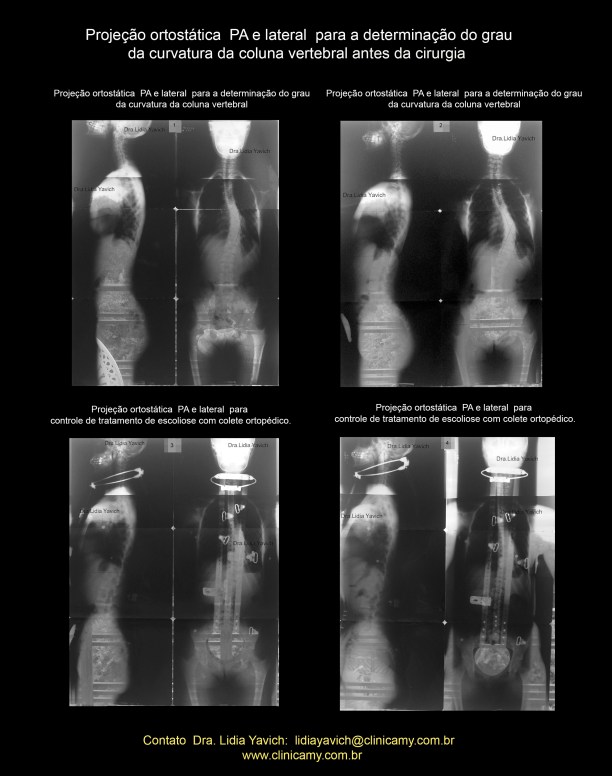

As radiografias panorâmicas da coluna foram fotografadas sobre o vidro de uma janela a luz do dia, motivo pelo qual se observa elementos da paisagem.

“Exames clínicos revelaram que a curvatura havia evoluído progressivamente e que esta aumentou mais que o dobro de tamanho, para aproximadamente para 45 graus. Na época, a solução proposta foi o uso de um colete cervical a fim de conter essa evolução.”

“O colete era utilizado 22 horas por dia, também foi recomendado aulas de natação para obter maior flexibilidade e ajudar na respiração, em caso de uma cirurgia.”

” Ao final, essa alternativa não se mostrou suficientemente eficiente, já que a curvatura evoluiu para 64 graus.”

LAUDO DO CONTROLE DO RX PANORÂMICO DA COLUNA VERTEBRAL APÓS A CIRURGIA:

Exame radiográfico efetuado para controle de tratamento cirúrgico de escoliose dorso-lombar de convexidade esquerda fixada através de hastes e parafusos metálicos.